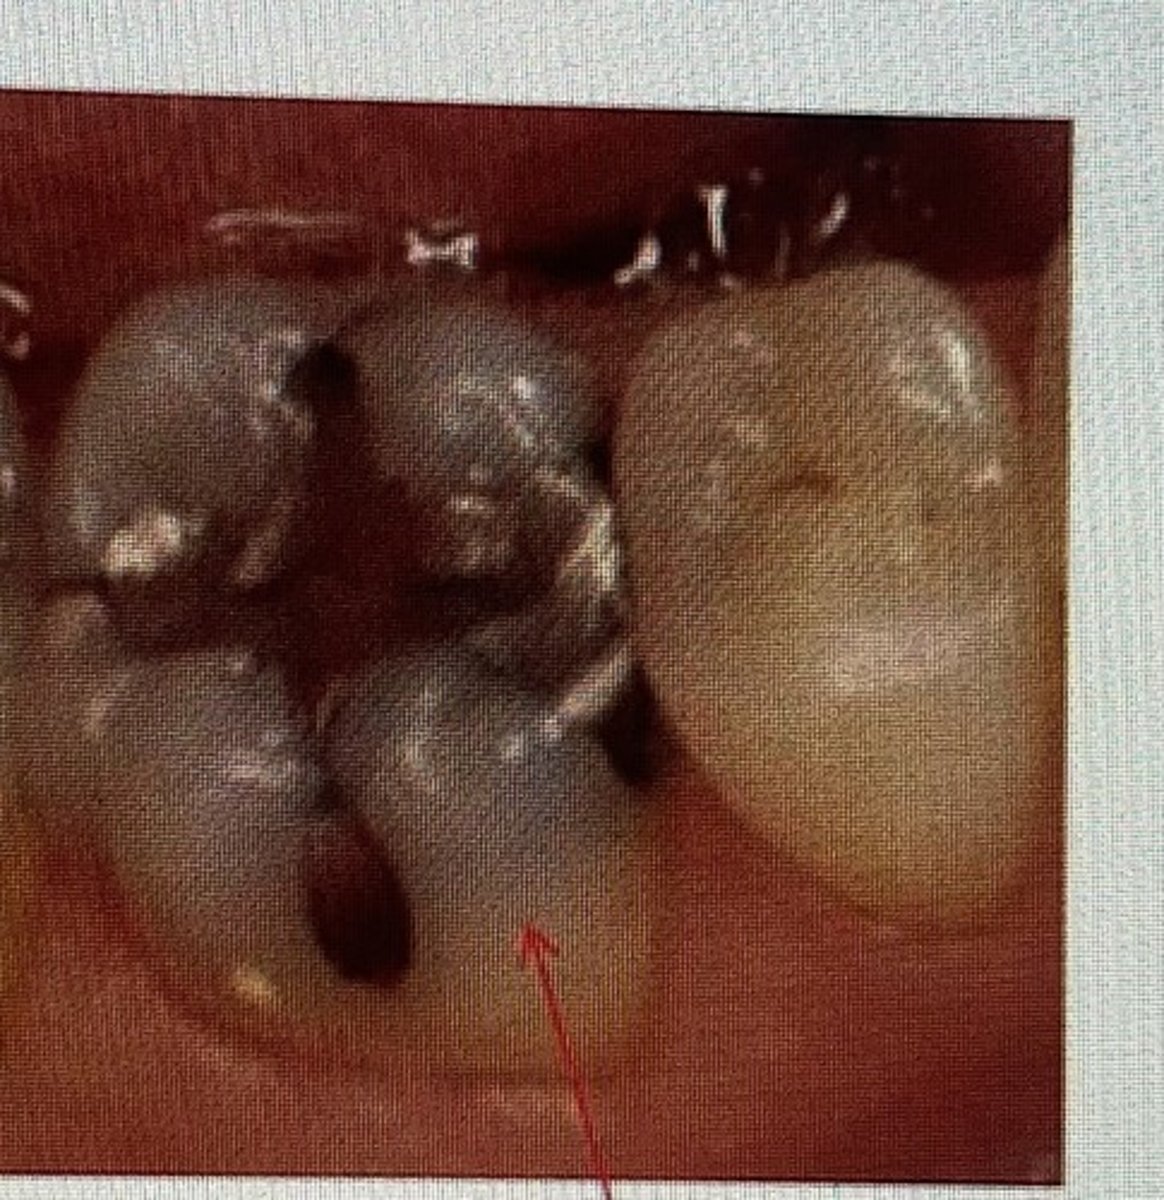

class II restoration